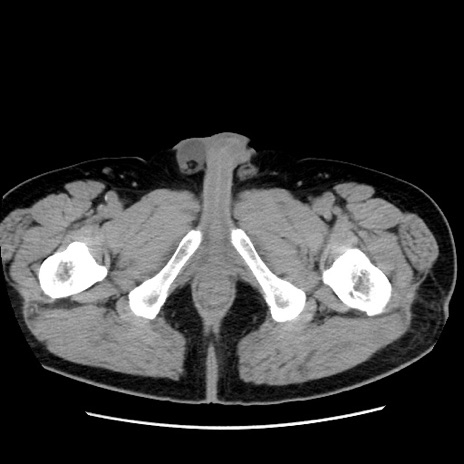

症例16(横断像)

【症例】 70歳代男性

【主訴】 腹痛、嘔吐

【現病歴】 約1ヶ月前より間欠的に腹痛と嘔吐あり、当院消化器内科を受診したところCTで多発する肝臓のLDAを指摘され、精査中であった。以降は消化器症状は安定していたが、2日前より嘔気と腹痛があり、同日より排便・排ガスが消失した。改善認めず、 本日、救急外来を受診した。

【既往歴】 大腸ポリープ切除後。

【身体所見】意識清明・会話良好、BT 36.3℃、BP 127/80mmHg、 P 80bpm、腹部:膨満あり、平坦・軟、上腹部正中および下腹部正中に圧痛あり、反跳痛なし、筋性防御なし。

【データ】WBC 7200、CRP 0.77